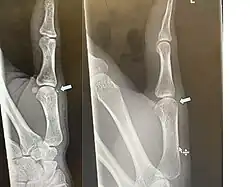

| Avulsion fracture of the proximal middle phalanx on the palm side | |

An avulsion fracture is a bone fracture which occurs when a fragment of bone tears away from the main mass of bone as a result of physical trauma. This can occur at the ligament by the application of forces external to the body (such as a fall or pull) or at the tendon by a muscular contraction that is stronger than the forces holding the bone together. Generally muscular avulsion is prevented by the neurological limitations placed on muscle contractions. Highly trained athletes can overcome this neurological inhibition of strength and produce a much greater force output capable of breaking or avulsing a bone.